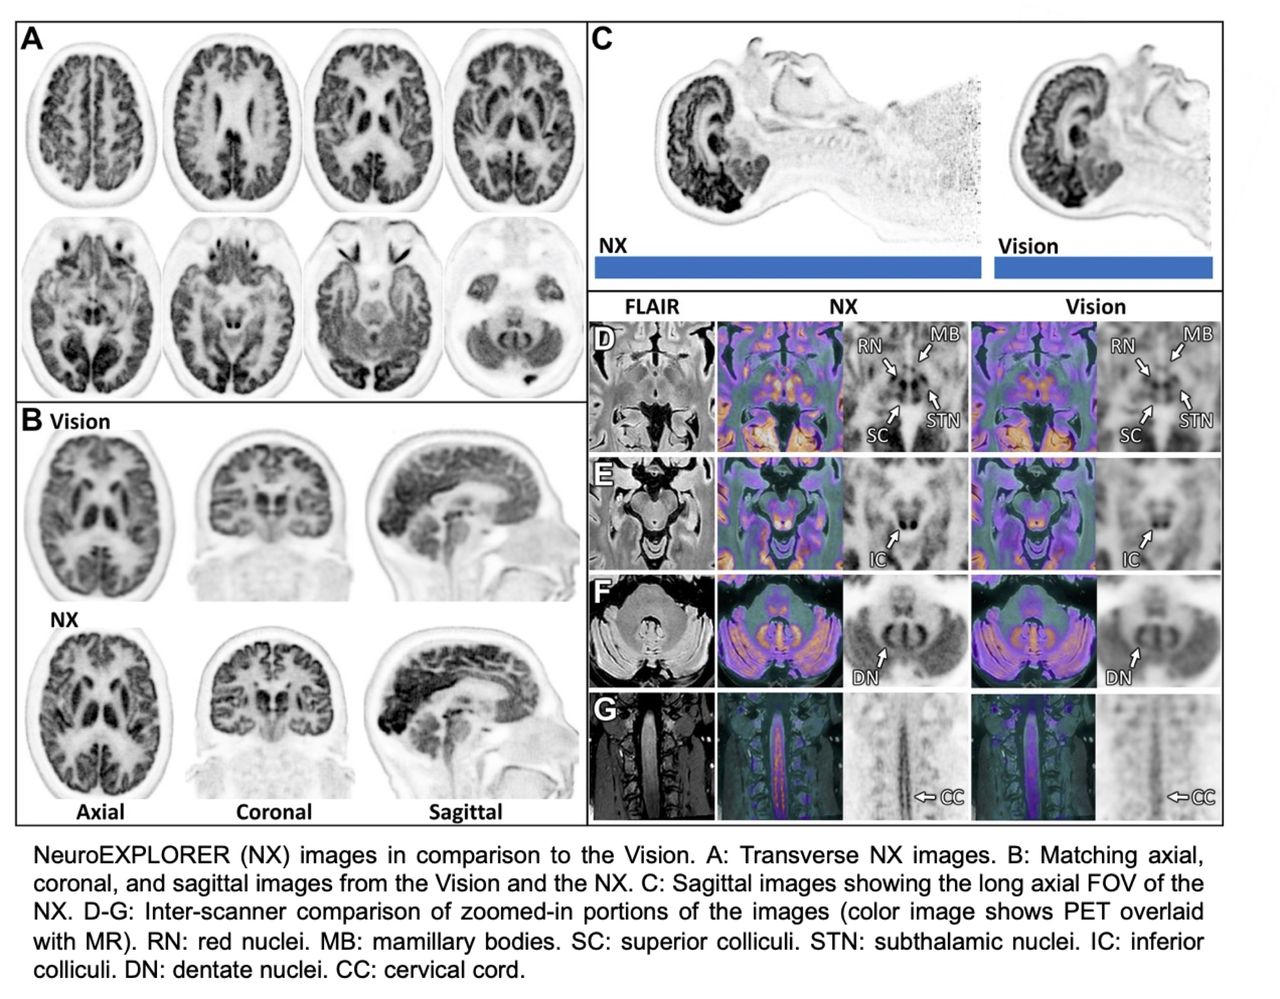

Esta imagen presenta una comparativa tecnológica entre dos sistemas de escaneo cerebral de alta precisión: modelo Vision y el nuevo NeuroEXPLORER (NX). NX representa un avance significativo porque ofrece una resolución mucho más nítida y un campo de visión más amplio, permitiendo observar el cerebro completo y parte de la médula espinal con gran detalle en una sola toma.

Las secciones de colores (D-G) muestran cómo se pueden identificar estructuras diminutas y específicas del cerebro, como los núcleos rojos o los cuerpos mamilares, con una claridad que antes era difícil de alcanzar, lo cual es fundamental para mejorar los diagnósticos médicos y la investigación científica.